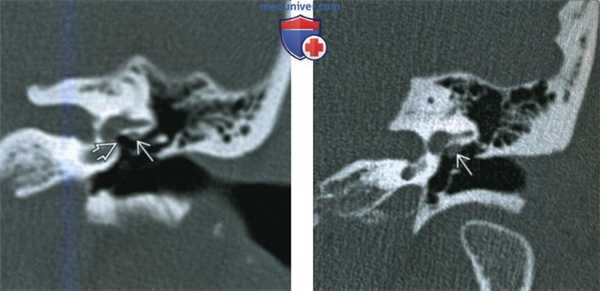

(Слева) При корональной КТ левой височной кости определяется нормальный барабанный сегмент лицевого нерва (поперечный срез) рядом с нижней поверхностью латерального полукружного канала. Обратите внимание на едва заметную костную стенку канала; оцените отношение к нише овального окна.

(Справа) При корональной КТ левой височной кости визуализируется очаговое объемное образование, исходящее из средней части барабанного сегмента лицевого нерва. Образование - выбухающий лицевой нерв, не шваннома. Выбухание лицевого нерва может приводить к значительным сложностям при стапедэктомии.

(Слева) При аксиальной КТ в костном окне у этого же пациента определяется протрузия барабанного сегмента ЧН VII в виде «гамака», натянутого в полости среднего уха. Обратите внимание на ЧН VII, достигающего ножки стремечка, что объясняет кондуктивную тугоухость.

(Справа) При корональной КТ левой височной кости визуализируется округлая мягкотканная структура, выбухающая из среднего барабанного сегмента ЧH VII. МРТ С+ позволяет различить протру-зию ЧH VII (не контрастируем) и шванному лицевого нерва (контрастируем).